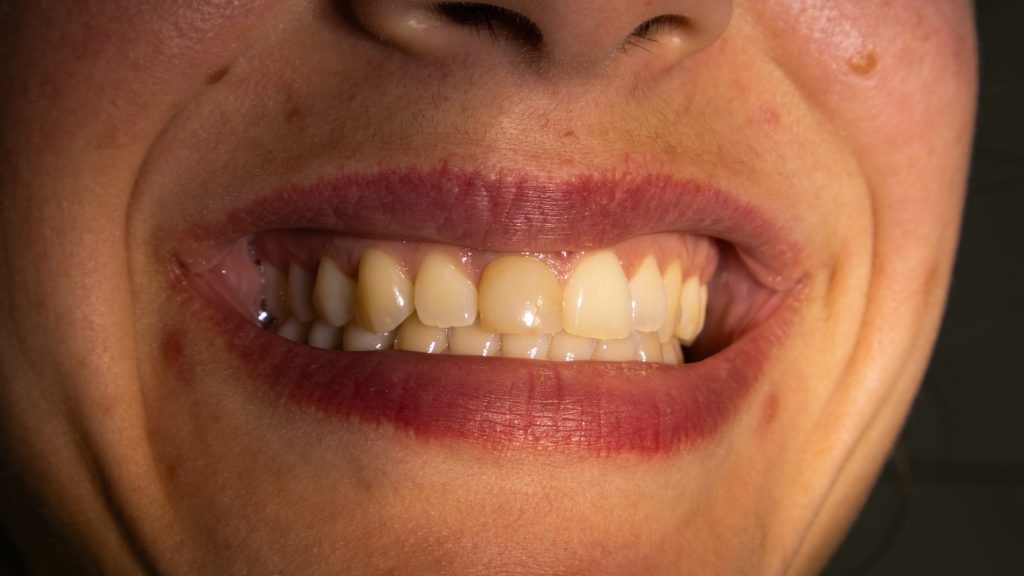

initial state